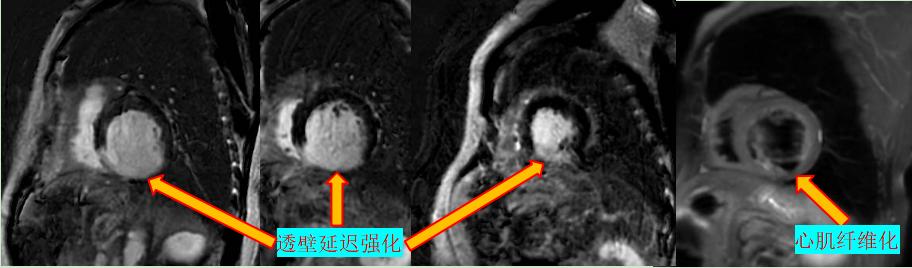

缺血性心肌?。盒呐K磁共振可以評估心肌活性,心肌組織中失去活性的心肌細(xì)胞和延遲強化存在可靠的對應(yīng)關(guān)系,即失去活性的心肌組織有延遲強化,如急性心梗或急性冠脈綜合征、慢性缺血性心肌病。

右冠狀動脈供血區(qū)透壁心梗伴心肌纖化

非缺血性心肌?。簲U張型心肌病、肥厚型心肌病、高血壓性心肌病、心肌淀粉樣變、心肌過度小梁化、限制性心肌病、心臟結(jié)節(jié)病、心肌炎等,心肌呈現(xiàn)不同程度條狀、斑片狀、斑點狀的延遲強化。